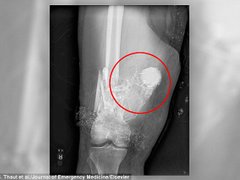

Bác sĩ gọi đội phá bom để gỡ pháo trong chân bệnh nhân

Các bác sĩ đã phải gọi đội phá bom mìn để giúp đỡ lấy một quả pháo chưa nổ găm trong chân bệnh nhân.

02/03/2018 03:56:59